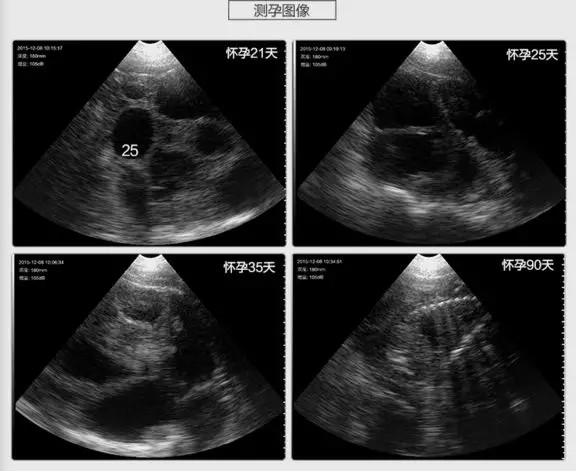

【前言】兽用B超作为母猪测孕的利器,在良种繁育中扮演着相当重要的作用。从第一时间检测是否怀孕到怀孕后检测胚胎数、有无死胎,是否有繁殖障碍疾病等方面都为养殖户提供了非常重要的参考信息,那么,作为猪仙子全新产品的无线兽用B超在母猪各个阶段到底发挥着怎样的作用呢:

1、第一时间检测出是否怀孕(第一个发情期:19-21天)

在这时检测出有无怀孕,对于养殖户来说是最省钱的,如果空怀可以及时再配,从而大大缩短了无效饲养的时间。

2、配种后30天左右估测胚胎数

作为规模化养殖场来讲,这是一个必须重视的指标。早期估测出来胚胎个数,有利于妊娠母猪日粮中营养配方以及饲喂量的调整。当胚胎个数较多而营养和日粮跟不上时,容易造成流产或弱胎;而当胚胎个数较少而营养和日粮过剩时,容易造成胚胎个体发育过大,引起难产。